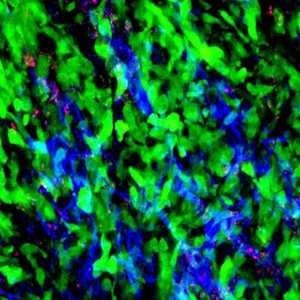

IVIM Tech imaging gallery

Lymph Node. Image Credit: Scintica Instrumentation Inc.

Lung. Image Credit: Scintica Instrumentation Inc.

Bone Marrow. Image Credit: Scintica Instrumentation Inc.

Skin. Image Credit: Scintica Instrumentation Inc.

Cancer Xenograft. Image Credit: Scintica Instrumentation Inc.

Cancer Metastasis. Image Credit: Scintica Instrumentation Inc.

Drug Distribution. Image Credit: Scintica Instrumentation Inc.

Cancer Drug Delivery. Image Credit: Scintica Instrumentation Inc.